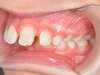

Cas 4 : Description

Chevauchement sévère. Traitement multibague sans extraction.

Avant

Après